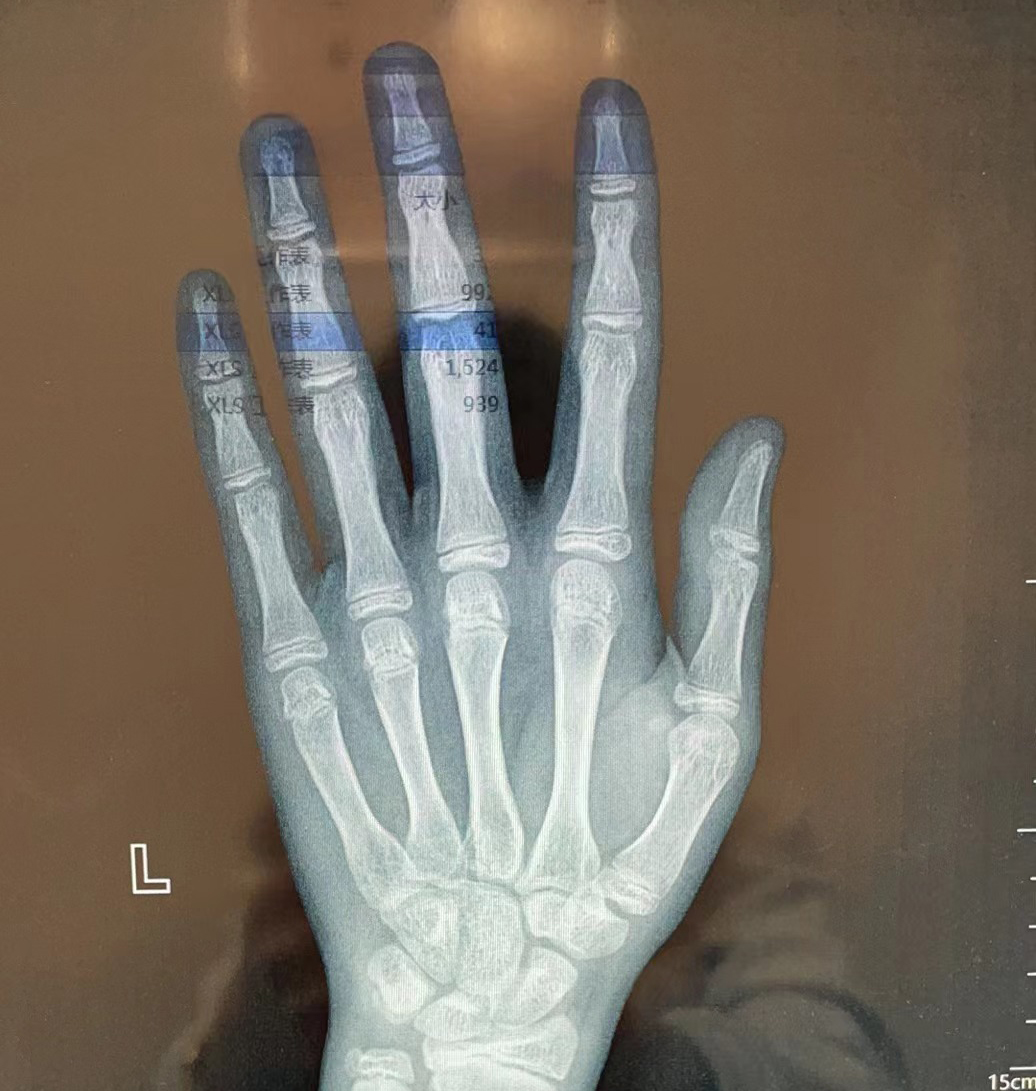

答:骨龄是通过拍摄左手正位x光片来测定,医生通过观察左手掌指骨,腕骨

在儿童发育阶段,根据实际需要进行骨龄测定,可了解儿童骨骼发育程度

由于手腕部骨成熟度指征与儿童的身高速度高峰密切相关,一般骨龄检测